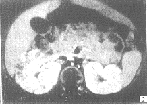

MRI检查:双肾增大,外形呈分叶状,皮髓质分界不清,呈长T1长T2信号,肝脏显著增大,脾脏轻度增大,注射Gd-DTPA后,双肾可见从乳头向皮质呈放射状排列的管状或条状强化影,肾盏肾盂内未见明显的造影剂(图2),此病例在超声引导下,行肝穿刺活检,结果提示肝纤维化。

图2 MRI注射Gd-DTPA,双肾

见从乳突向皮质呈放射状排列的管状高信号影,肾盂肾盏未见造影剂

关于本病的MRI表现,笔者未见正式报道,本组例1、2作MRI检查,均行平扫加增强扫描,例1具有典型的表现双肾增大、呈分叶状、皮髓质分界不清,呈长T1、长T2信号,注射Gd-DTPA后表现为双肾乳头至皮质呈放射状或车轮状排列的条状高信号影,类似分泌性尿路造影表现,例2 MRI与例1表现不同。例1年龄小,病变广泛,例2年龄大,病变范围小,说明不同类型的婴儿型多囊肾表现不尽相同。